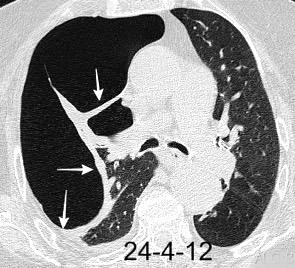

VIH+. 1 mes antes derrame pleural en el curso de una

infección